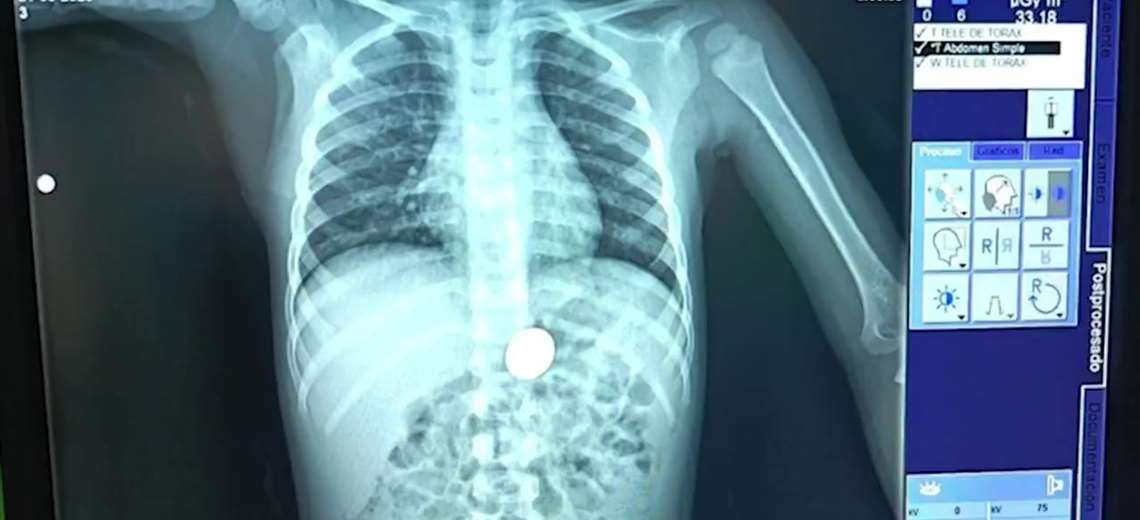

Familia vive angustia: niño traga moneda de ₡10 y es atendido de emergencia

Este hecho enciende las alertas: Solo el año pasado, 102 niños fueron hospitalizados por ingerir cuerpos extraños.